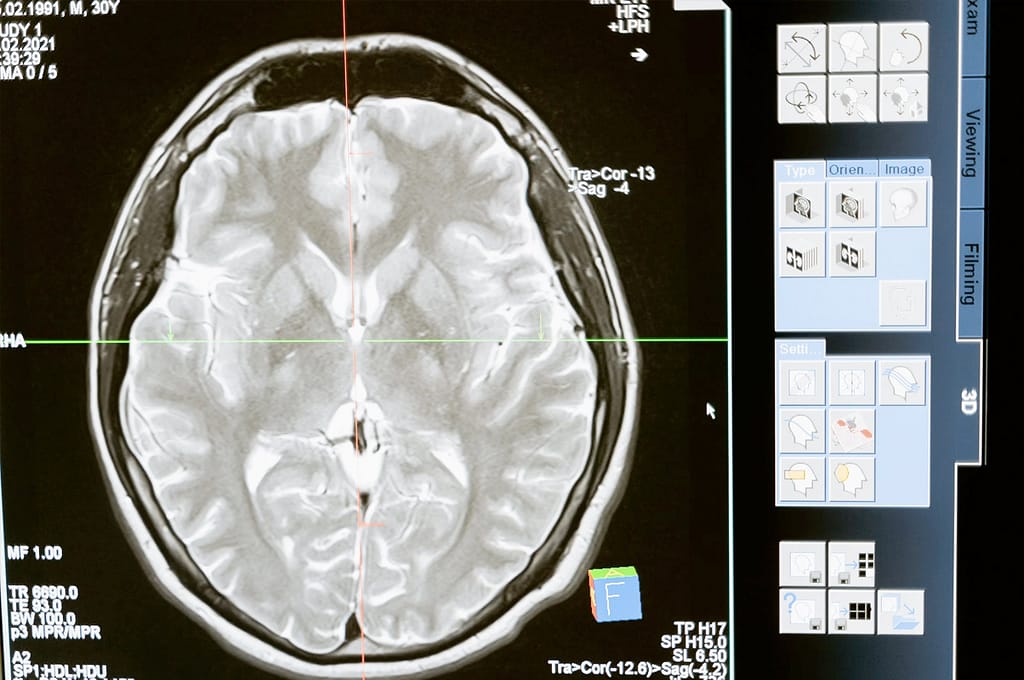

A radioterapia, também conhecida como radioterapia, é o uso de ondas de alta energia para destruir as células cancerígenas. O tipo de ondas usadas na radioterapia são chamadas de radiação ionizante. A radiação ionizante pode danificar o DNA, o que pode levar à morte de células cancerígenas.

A radioterapia é mais comumente usada para tratar o câncer que se espalhou para outras partes do corpo (câncer metastático). Também pode ser usado para encolher um tumor antes da cirurgia ou após a cirurgia para matar as células cancerígenas remanescentes.